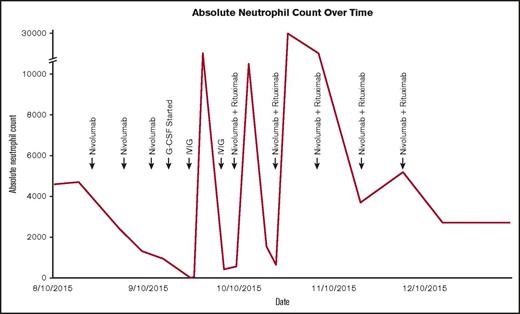

ANC over time following initiation of nivolumab and subsequent interventions.

The patient maintained normal organ function and performance status at the time of nivolumab initiation despite multiple lines of multiagent chemotherapy, and her starting absolute neutrophil count (ANC) was 4700 cells/mm3. The patient tolerated therapy very well but was noted to have an ANC of 950 cells/mm3 at the time of her third dose. Granulocyte-stimulating colony factor was initiated 1 week later after her ANC decreased to 180 cells/mm3. Pathologist review of the peripheral blood smear showed absolute neutropenia without blasts or signs of dysplasia. Although not previously reported, we were suspicious for autoimmune neutropenia knowing the immune-related effects of nivolumab, temporal association with medication administration, and absence of other etiology. Despite 4 days of granulocyte-stimulating colony factor, her neutrophil count plummeted to 0. We then administered IV immunoglobulin (IVIG) and temporarily held nivolumab. Blood was taken to assess for antineutrophil antibodies prior to initiation of IVIG and ultimately found to be positive.

The patient’s ANC markedly improved within 3 days, but recovery was transient and required another dose of IVIG 11 days after the first dose (Figure 1). Computed tomography showed a pronounced partial response where no therapy had successfully worked before. It was for this reason that nivolumab was restarted in addition to rituximab to preemptively treat autoimmune neutropenia. The patient never again experienced neutropenia and ultimately developed a complete remission within 4 months (Figure 2). Now 18 months from remission, she has remained relapse free with normal blood cell counts at the time of this article’s submission.